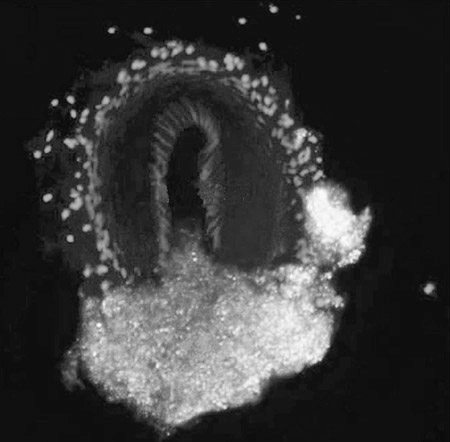

研究人员在后腿动脉——向后腿传送血液的大血管——上有一道伤口的小鼠身上测试了这种微粒的效果。结果显示,这些伤口自我愈合大约需要4分钟的时间,然而通过在出血后进行人造血小板的静脉注射,使小鼠的失血时间缩短了23%。研究人员在最新出版的美国《科学—转化医学》杂志上报告了这一研究成果。研究人员发现,小鼠凝结的伤口被这些球形微粒所填满,表明它们对动物自身的血小板愈合提供了帮助。